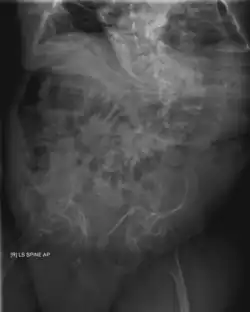

OI—especially its severe form, type III—also has effects on the gastrointestinal system. It was found to be associated with recurrent abdominal pain and chronic constipation in two studies on patients affected by OI.[40][41] Chronic constipation is especially common,[1]: 377 and is thought to be aggravated by an asymmetric pelvis (acetabular protrusion).[1]: 377 [41] Especially in childhood, OI-associated constipation may cause a feeling of fullness and associated food refusal, leading to malnutrition.[1]: 377

Diagnosis is typically based on medical imaging, including plain X-rays, and symptoms. In severe OI, signs on medical imaging include abnormalities in all extremities and the spine.[97] As X-rays are often insensitive to the comparatively smaller bone density loss associated with type I OI, DEXA scans may be needed.[5]: 1514